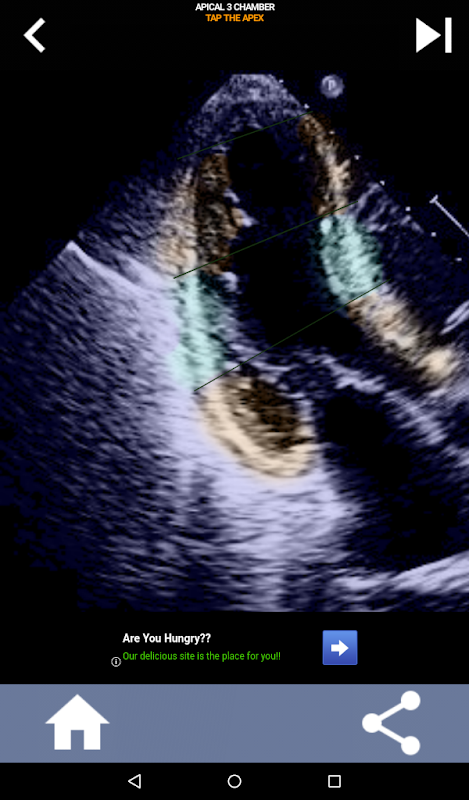

วิธีการใช้ภาพแบบทดสอบเพื่อเรียนรู้ส่วนหัวใจ AHA: Echocardiography

การทำความเข้าใจเกี่ยวกับส่วนของหัวใจ AHA (American Heart Association) มีความสำคัญสูงสุดสำหรับนักตรวจคลื่นเสียงหัวใจในการสื่อสารกับแพทย์โรคหัวใจที่เขียนรายงานได้อย่างมีประสิทธิภาพ เมื่อทราบบริเวณทางกายวิภาคเฉพาะและส่วนที่สอดคล้องกัน ช่างภาพสามารถอธิบายและสื่อสารความผิดปกติหรือสิ่งที่ค้นพบได้อย่างถูกต้อง ทำให้มั่นใจได้ว่าการสื่อสารที่ชัดเจนและรัดกุมระหว่างผู้เชี่ยวชาญทั้งสอง

ความเข้าใจนี้มีความสำคัญอย่างยิ่งเมื่อแพทย์โรคหัวใจพยายามค้นหาตำแหน่งที่แม่นยำของปัญหา หรือเมื่อแพทย์ที่โทรเรียกพบปัญหาภายในพื้นที่หนึ่งๆ กระตุ้นให้ผู้ตรวจวิเคราะห์ด้วยคลื่นเสียงแสดงส่วนที่เกี่ยวข้องอย่างแม่นยำ เช่น ผนังกึ่งกลางด้านล่าง ดังนั้น การมีความเข้าใจที่ครอบคลุมในส่วนของหัวใจ AHA จึงเป็นชุดทักษะที่จำเป็น

แอปนี้จะทดสอบความรู้ของคุณโดยใช้ภาพสะท้อนจริง ซึ่งฉันมักจะพบว่าเป็นวิธีการสอนที่ดีที่สุด